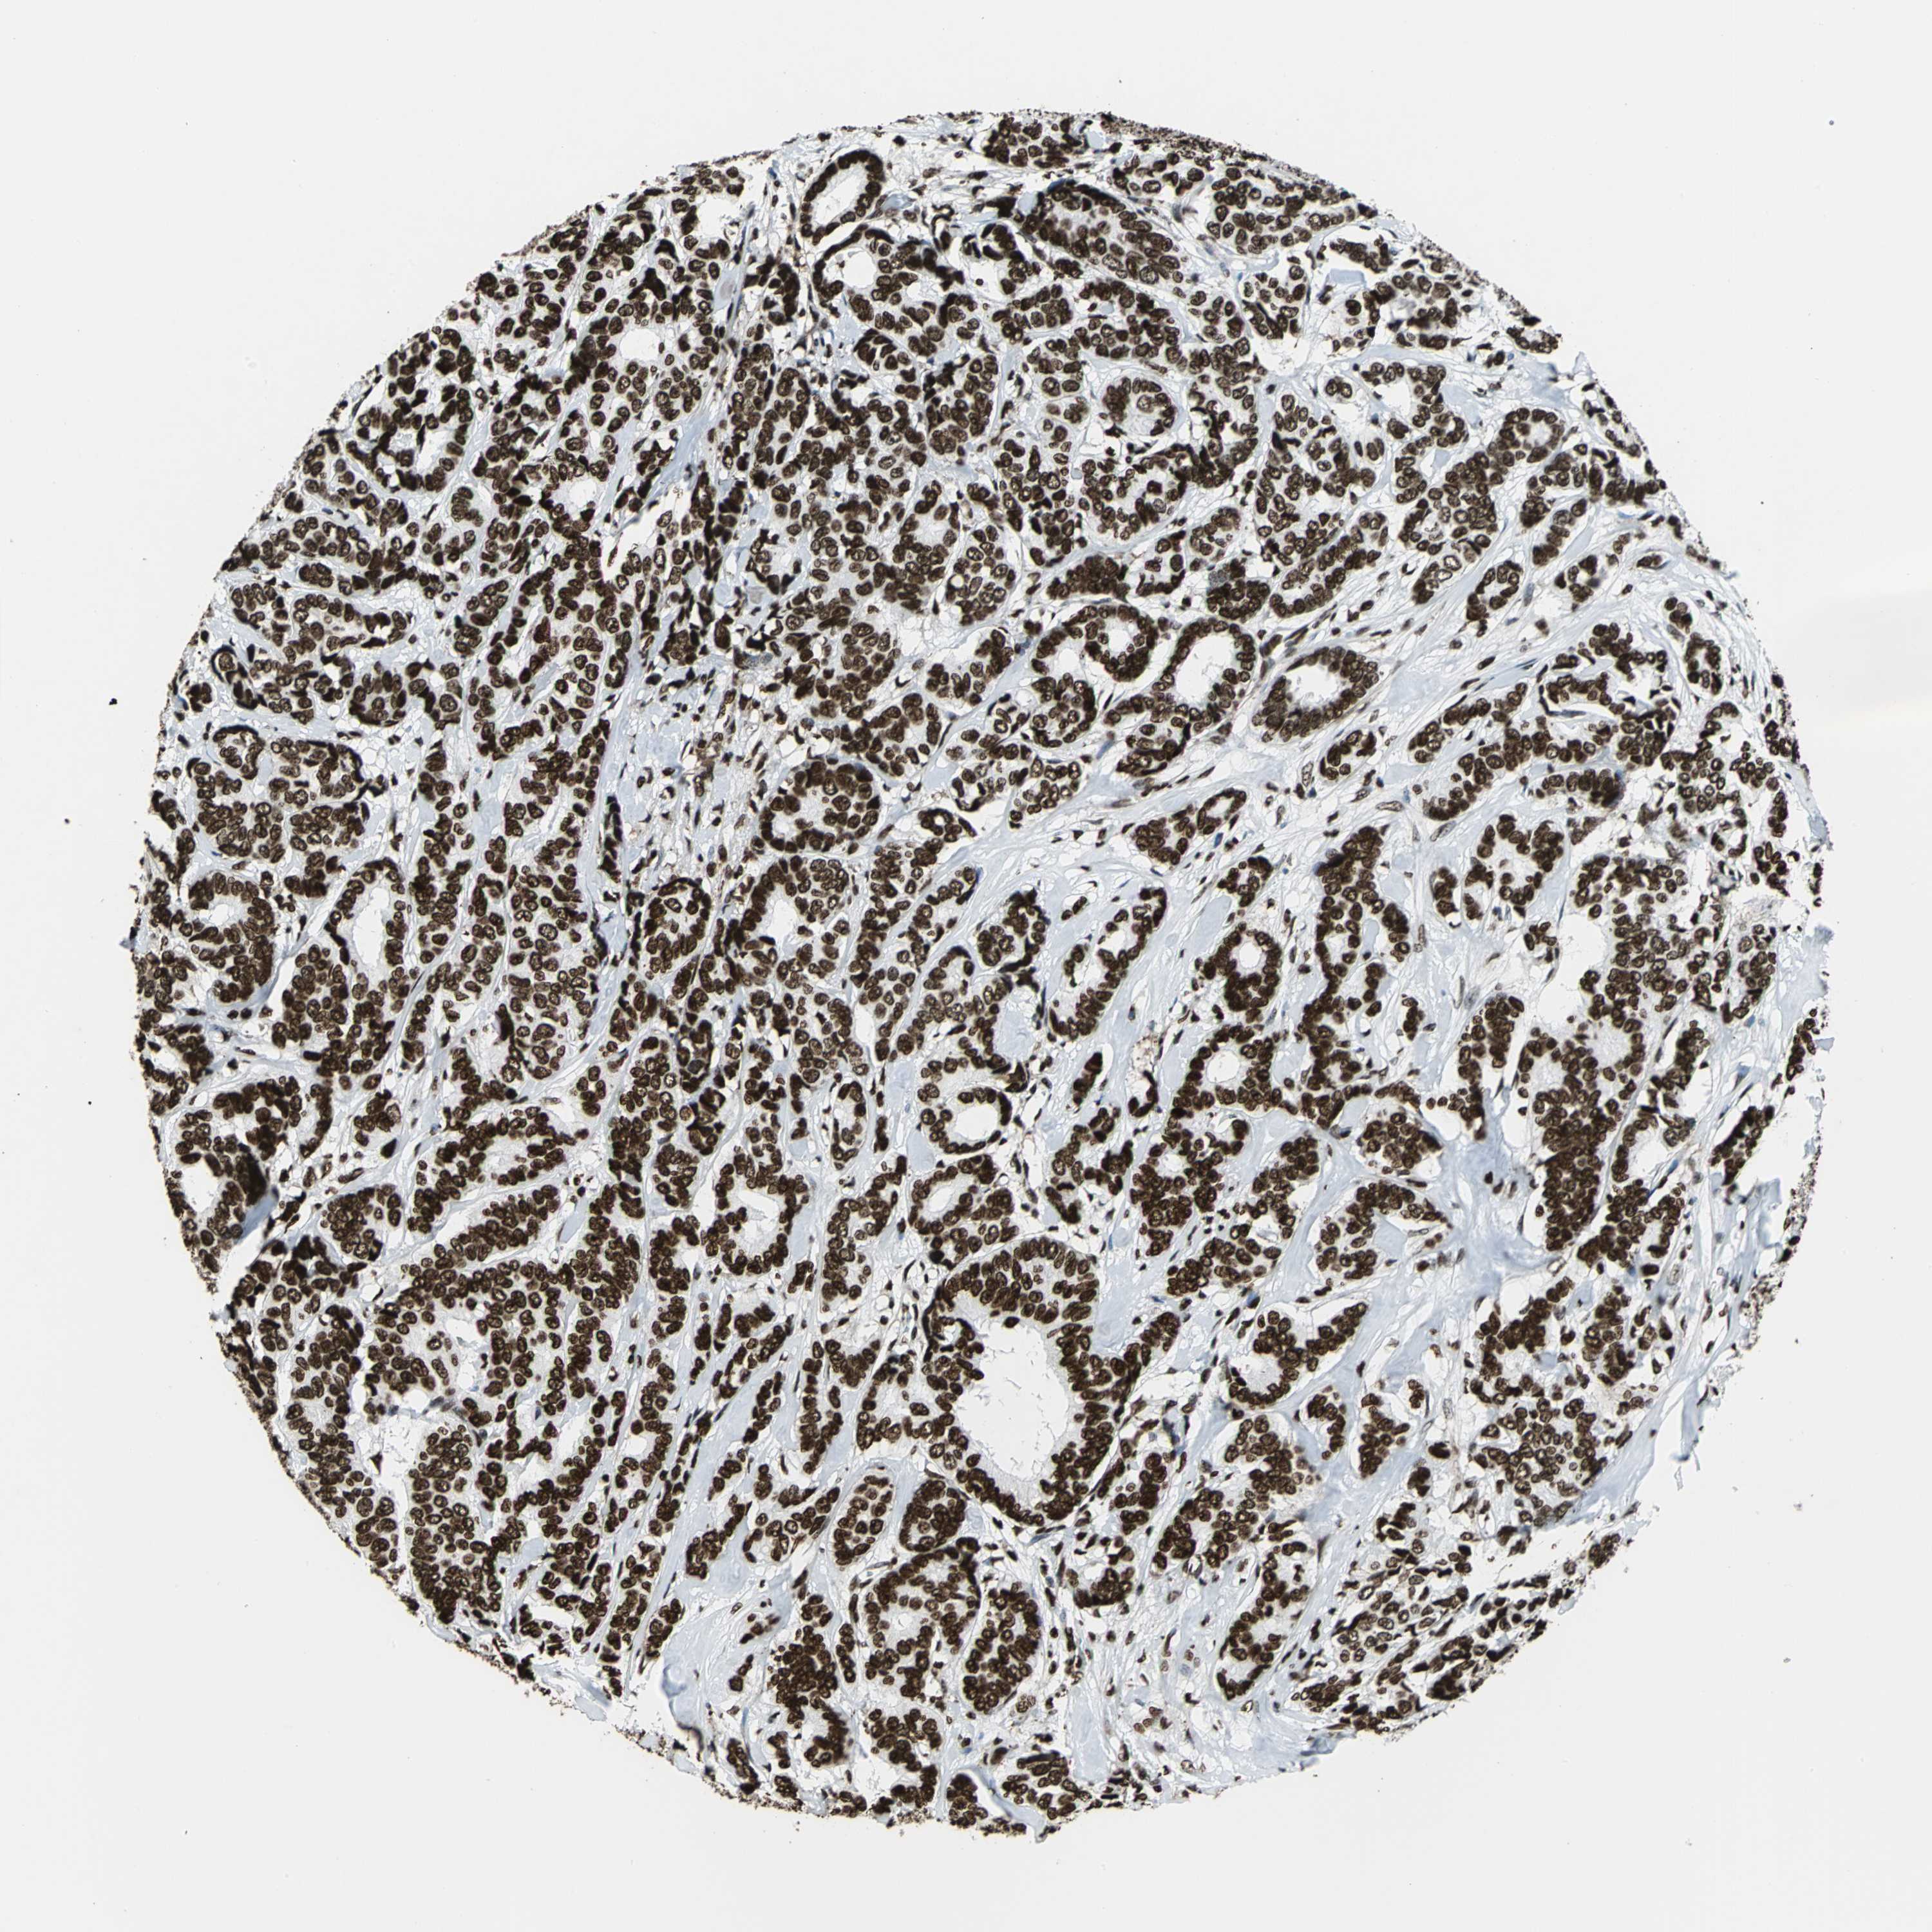

APEX1

CANCER BREAST CANCER Show tissue menu

BRCA TCGA BRCA VALIDATION PROTEIN EXPRESSION

ANTIBODIES

AND

VALIDATION